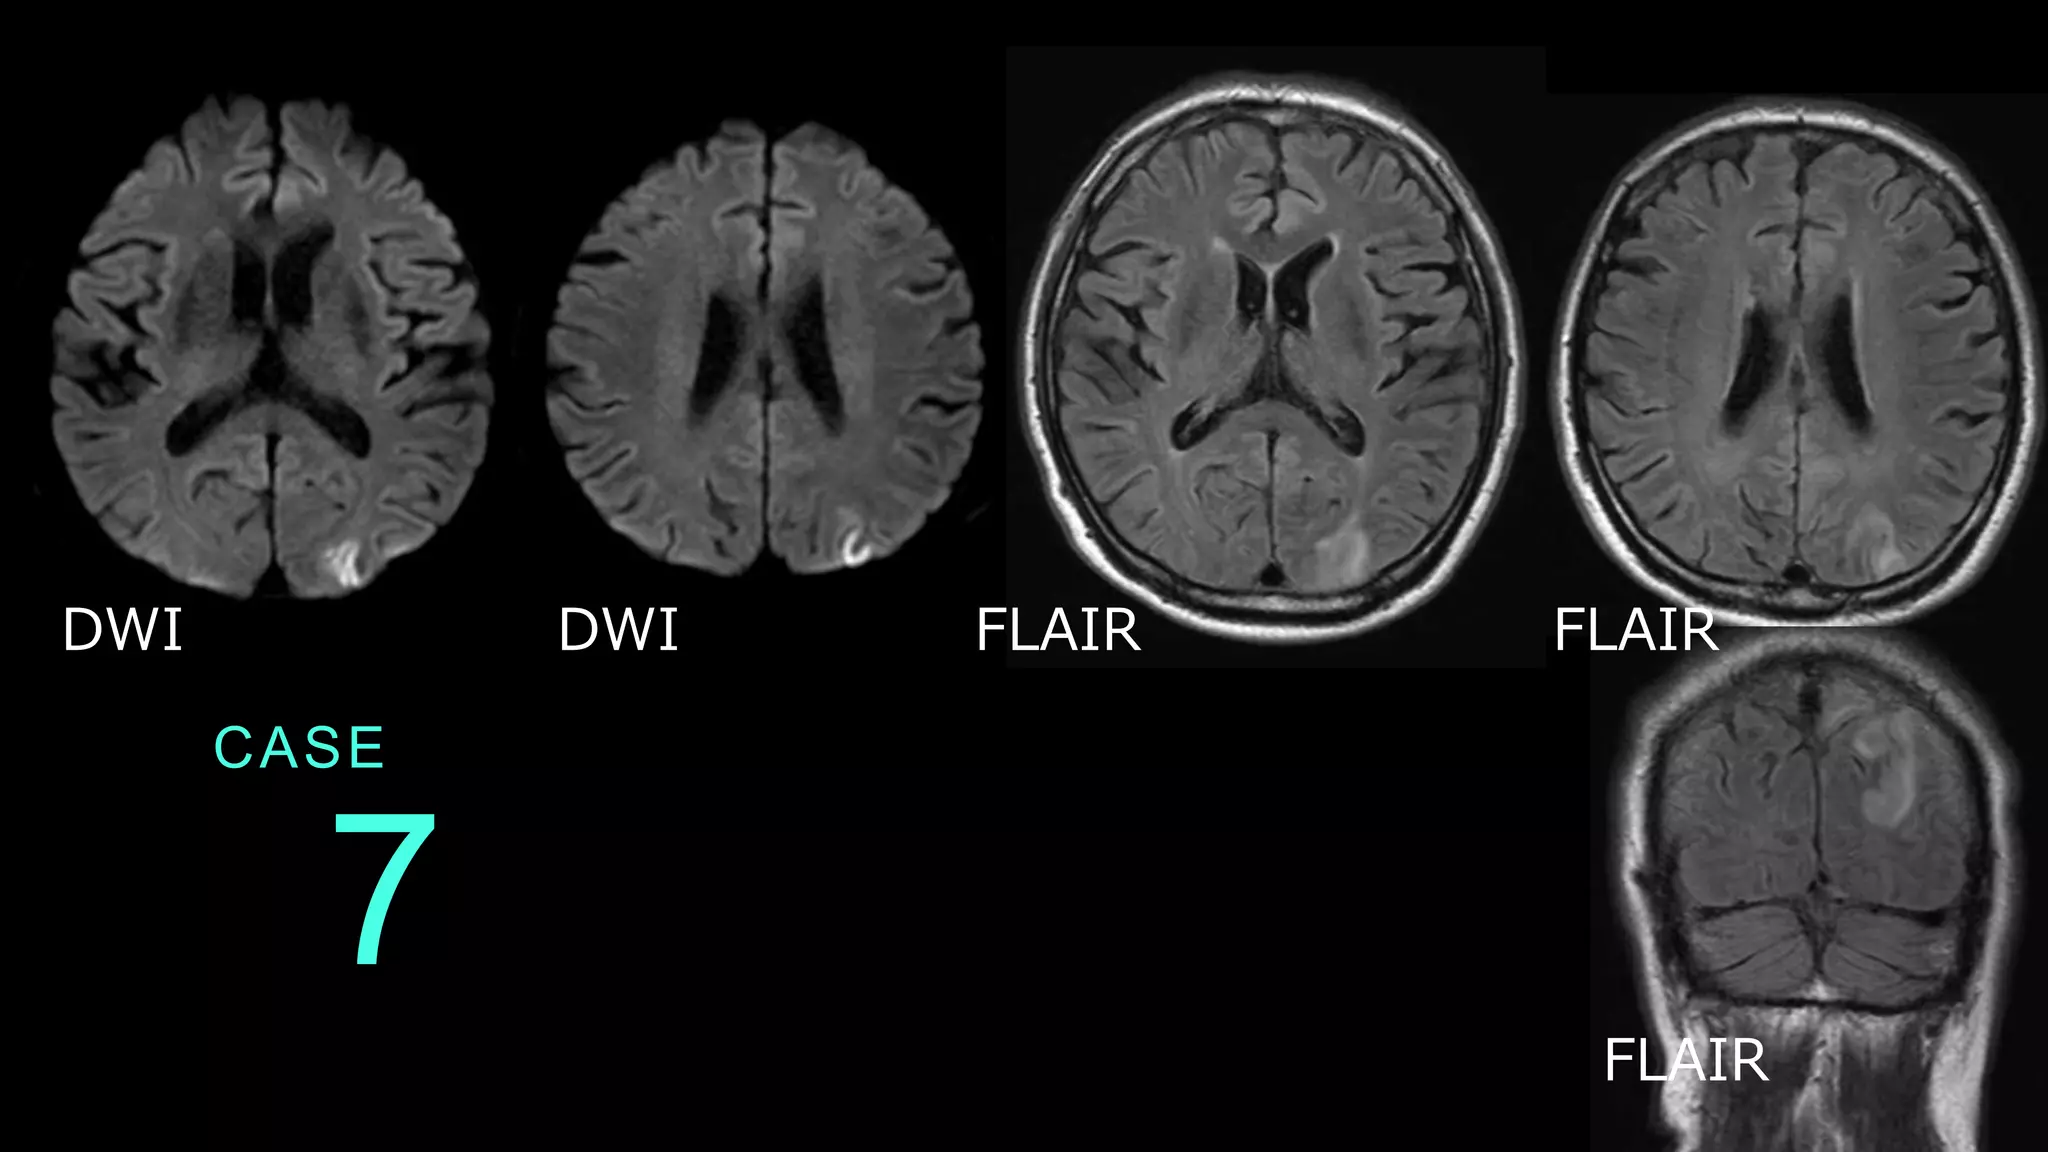

CASE 7 DWI DWI FLAIR

FLAIR FLAIR

CASE 7 DWIでは左の後頭葉と頭頂葉皮質の高信号変化あり。 FLAIRではDWI病変の皮質を含む白質の淡い高信号変 化を認める。 DWI DWI

CASE 7 コメント:脳炎症例。 DWI所見よりもFLAIR所見の方が広い。 ここまでの脳梗塞症例とは画像の違いがわかる。